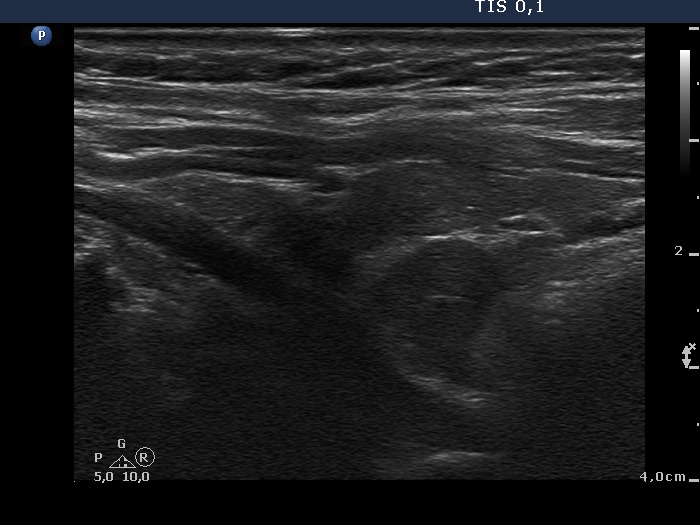

Ultrasonography. The thyroid was minimally-moderately hypoechogenic. There was a hyperechogenic nodule in the central part of the right lobe while several small insignificant lesions in the left thyroid. There was a hypoechogenic mass in the border of the middle-lower part of the right lobe dorsolateral. The lesion presented no vascularity.

Left lobectomy was performed with the removal of the right lower parathyroid. Histopathology: benign, hyperplastic nodule and parathyroid adenoma corresponding to the right lower parathyroid.